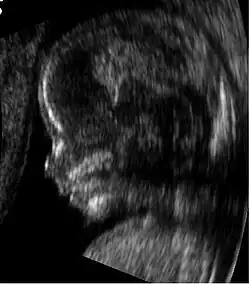

- Ressonância magnética (RM) sem meio de contraste em RM e ultrassonografia obstétrica não estão associadas a nenhum risco para a mãe ou para o feto e são as técnicas de imagem de escolha para gestantes.[1]

Ressonância magnética

A ressonância magnética (RM), sem meio de contraste em RM, não está associada a riscos para a mãe ou o feto e, juntamente com a ultrassonografia médica, é a técnica de escolha para exames de imagem na gravidez.[1]